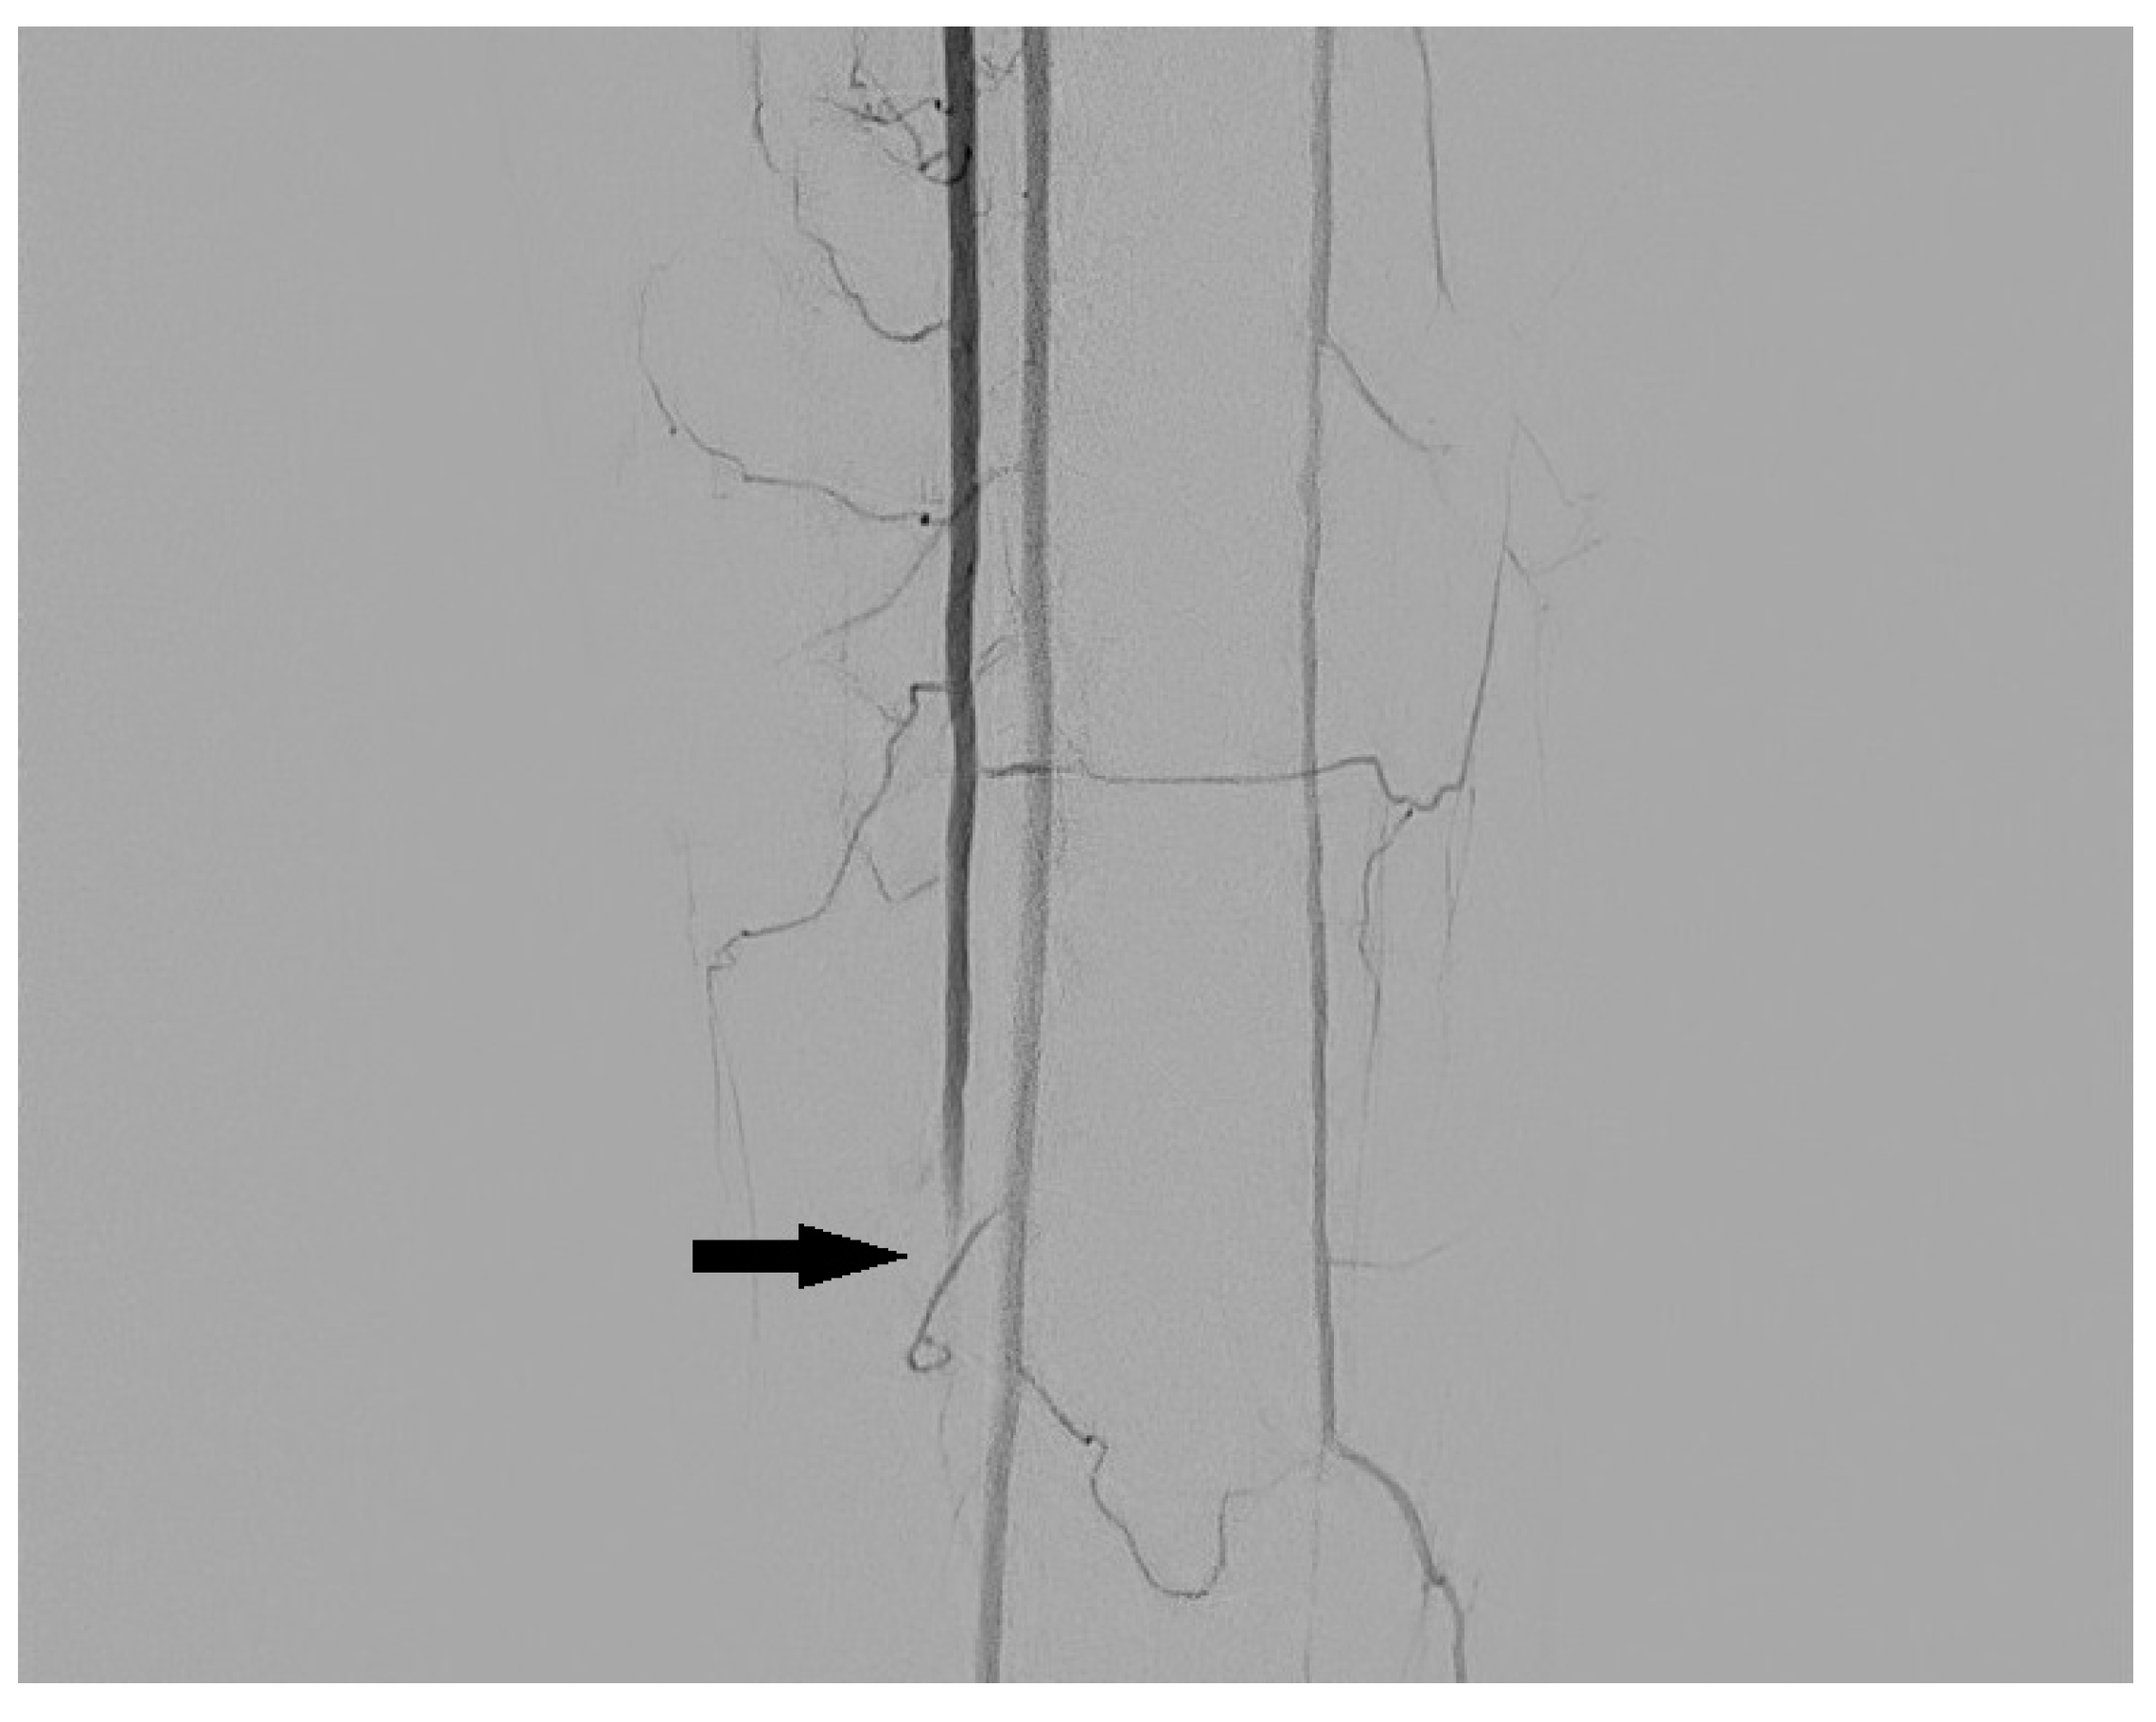

3.3. Arteriovenous Fistula